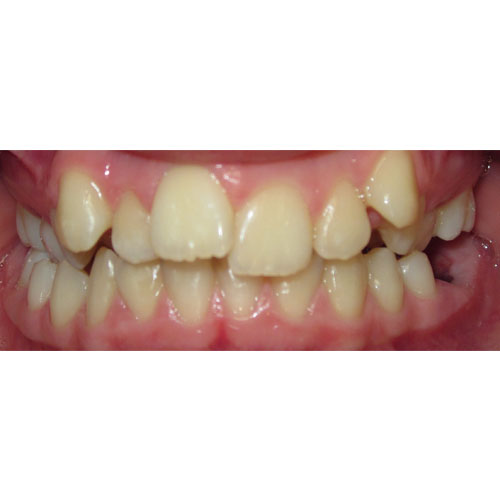

Nasze rezultaty